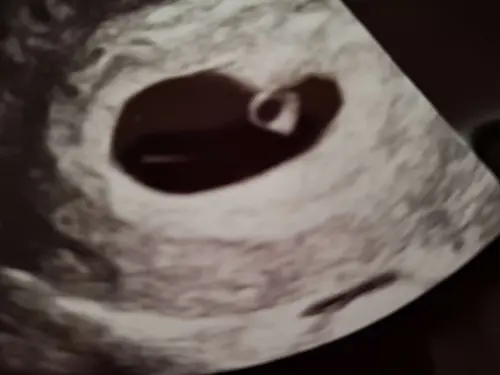

Helaas heb ik geen goede ervaring met je te delen. Ben zelf momenteel ook weer in afwachting van of toch een vitale zwangerschap of een 3e miskraam.

Dit is voor mij de reden geweest dat ik nooit weer een vroege echo zou doen. Geeft veel onzekerheid. Vorige zwangerschap bleek ik 2 weken minder ver te zijn dan verwacht. Dat het zou wel kunnen. Sterkte met wachten en hopelijk valt het de goede kant op.

Ik denk dat er nog wel hoop is! Ik heb met 6+2 een echo in het zkh en ze zei tegen mij dat het kan dat we een hartje zien kloppen, maar dat het ook zeker mogelijk is dat we net iets te vroeg zijn. Ze zullen dat vast vaker meemaken rond dat moment, anders zeiden ze het niet. Wanneer heb je een volgende echo? Kan me voorstellen dat jij je wel erg zorgen maakt❤️

Jep. Hadden ze tegen mij ook gezegd inderdaad. Maar een week verschil is gewoon zo groot.

Ik mag pas over 10 dagen weer komen. Dan moet het verschil zo groot zijn dat ze kunnen zeggen of het wel of niet goed is.

Vreemd dat ze die conclusies gelijk trekken, lijkt mij eerder dat het 3 dagen ofzo heeft afgeweken dus dat je wellicht 6 weken zwanger bent en je nog net geen kloppend hartje kon zien. Jammer dat je pas over 10 dagen mag terugkomen! Loop je via het zkh of vk? Als je via het zkh loopt dan kan je waarschijnlijk voor een vroege echo terecht bij de vk.

Mijn verhaal was helaas iets minder mooi in februari… ik had telkens een klein beetje bloedverlies en mocht langskomen voor een echo omdat ik zo ongerust was. Ik had toen bijna 7 weken moeten zijn. Ik ben toen terug gezet naar 5 weken en 2 dagen maar er was wel een hartslag. Ik kreeg helaas na 3 dagen een miskraam